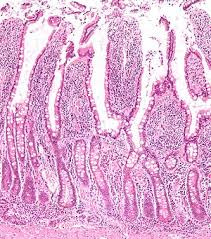

腸管粘膜にある絨毛(じゅうもう)は、有害物質から身体を守る「腸管バリア機能」という働きをしています。この絨毛は、下剤を使えば使うほど炎症がおきて短くなり、腸の働きを低下させてしますのです。

絨毛WIKIより